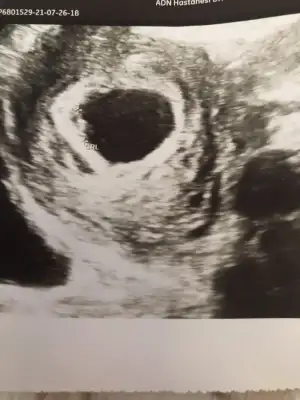

Karindan ise erkek gorunuyor vajinal ise kizIkra meyra canım bakabılır mısın 5+5 haftalık

Teşekkürler canım kesede ki konumuna göre mi anlıyorsunuzKadından ise erkek gorunuyor vajinal ise kiz

Kadından ise erkek gorunuyor vajinal ise kiz

Kese konumu pek tutmuyor karından ise erkek gorunuyor vajinal ise kız6 haftalık iken şuan 11 haftalık